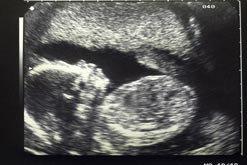

Ultrasound scans have become almost standard for pregnant women. But are they really justified?

For a large number of pregnant women, the scan which shows their unborn baby wriggling its feet and sucking its thumb is one of the most important milestones. But Hylton Meire, an eminent radiologist, has started a debate on whether the scans are really justified. Writing in the journal Ultrasound, Dr Meire argues that not only is there scant scientific evidence to prove that the 20 week scan is worth doing, he also questions the reliability of the standard method of testing for Down’s Syndrome – the nuchal fold measurement – which is taken during the earlier, 12 week scan. But is there value in knowing, in advance, if there is a risk of abnormality for your unborn child? And how can parents be supported through the difficult decisions if a risk is identified?